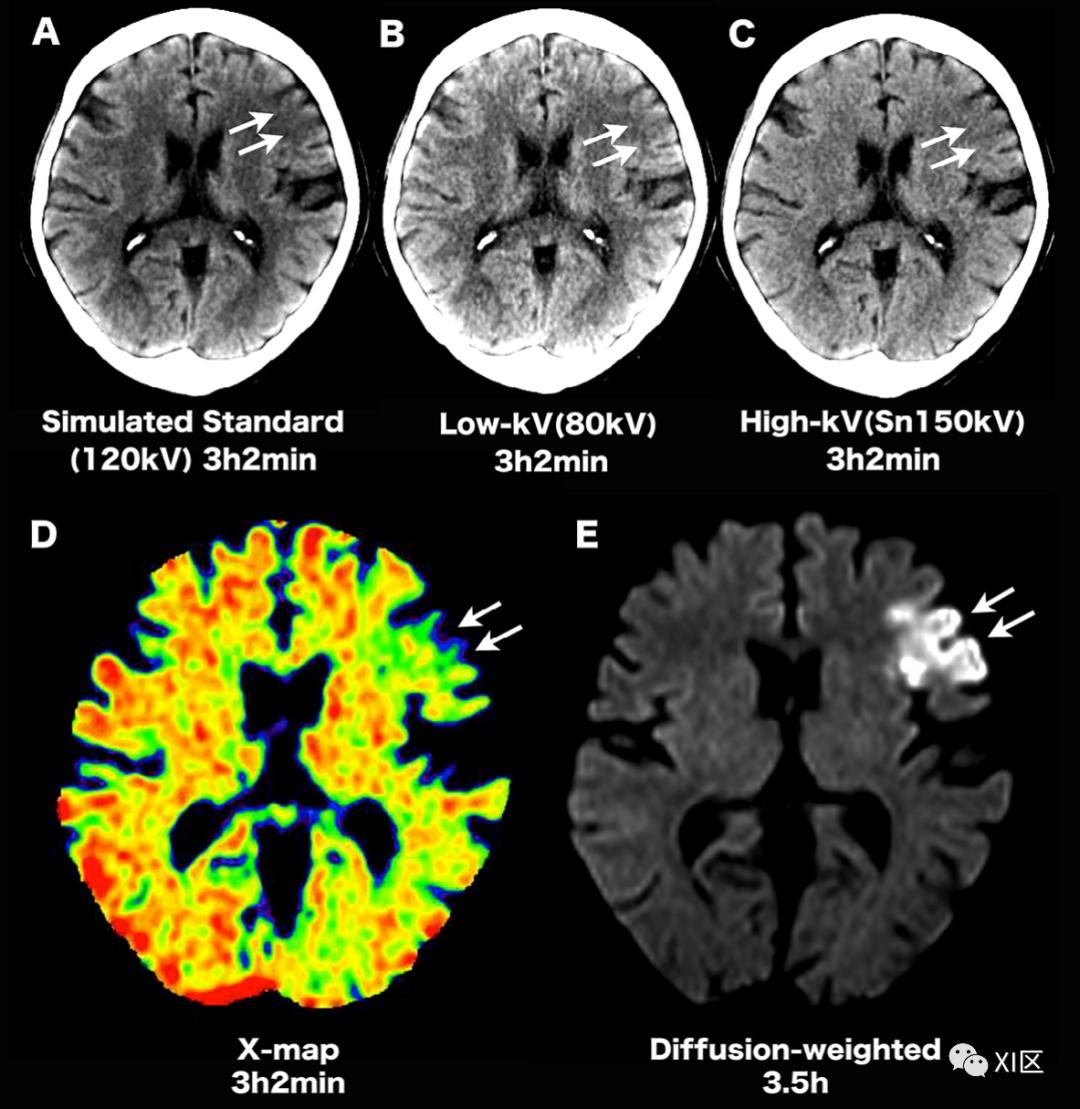

双能CT扫描产生的水肿图像有助于检测急性缺血性脑卒中。

对于急性缺血性脑卒中的诊断和治疗,灰质水肿的检测至关重要;据报道,双能量CT扫描生成的水肿图非常有用。“X-map”是一种在平扫双能CT扫描中识别急性缺血性病变的应用,它使用三种物质分解创建了一个虚拟的灰质和水含量图。X-map上的病变清楚地反映了急性缺血性脑卒中引起的脑水肿的含水量。X-map和扩散加权图像上的结果之间有很好的相关性。该方法将有助于急性缺血性卒中患者早期制定治疗策略。

图19 急性缺血性脑卒中。(A-C)发病后3小时2分钟获得的混合、低千伏和高千伏图像显示左额叶出现早期症状(箭头)。在检测急性缺血性病变时,混合等同于高千伏,低千伏低于混合和高千伏。(D)发病后3小时2分钟获得的X-Map显示,与标准CT相比,左额叶的明确异常(箭头所示)。(E)发病3.5小时后获得的扩散加权MRI显示左额叶异常信号(箭头)。肝脂肪分数与肝纤维化评估